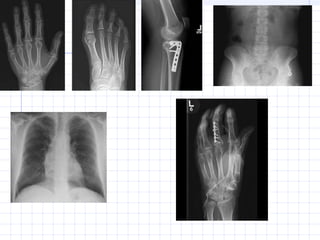

X-Ray History El públicoestaba fascinado con los rayos x, y el mundo médico reconoció inmediatamente la extraordinaria importancia del descubrimiento. En los meses siguientes, una gran cantidad de anatomías y fracturas fueron radiografiadas. Paralelamente a las aplicaciones médicas, las industriales también fueron desarrolladas

X-Ray History Para losprimeros años se utilizaron “Pantallas Fluoroscentes”. Era común utilizarlas sin mayor protección debido a que no se conocía que los rayos x eran capaces de ionizar o destruir celulas vivas. El uso de películas radiográficas que requieren exposición y revelado fueron introducidas un tiempo luego (alrededor de 1912). Los intensificadores de imágenes, que permiten observar una imagen en tiempo real fueron introducidos en 1950. Finalmente los detectores de rayos X, utilizados en muchos equipos hoy en día fueron introducidos a finales de la década de los 60. ( TAC y otros )